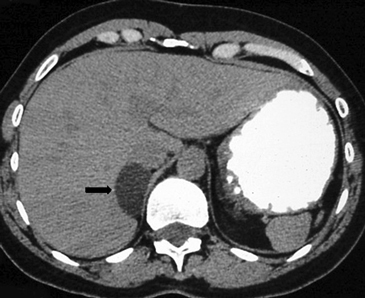

BLos márgenes de la lesión pueden ser una característica útil, los contornos irregulares se asocian a una mayor probabilidad de malignidad. Sin embargo, las metástasis, especialmente si son pequeñas, pueden presentar una morfología muy similar a la de un adenoma (Figura 6), vale decir homogéneas y de bordes bien delimitados. Se ha descrito también que la preservación de la morfología adreniforme usualmente se asocia a benignidad (Figura 7 a y b).

Figura 6. Lesión homogénea, de contornos bien delimitados (flecha) visualizada en tomografía computada sin contraste realizada en contexto de estudio de diseminación de cáncer mamario. A pesar de los caracteres morfológicos aparentemente benignos, se demostró que la lesión correspondía a una localización secundaria.